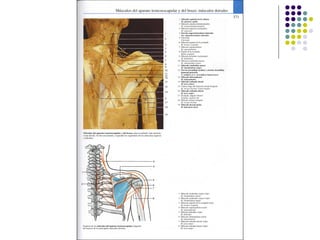

La extremidad superior humana incluye el hombro, el brazo, el codo, la muñeca y la mano. Está diseñada para una variedad de funciones motoras finas como agarrar objetos y realizar tareas manuales complejas. La coordinación precisa de los músculos y los huesos de la extremidad superior es clave para su versatilidad funcional.